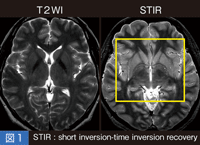

位相イメージングとは、局所の位相変化や位相差を積極的に利用する手法であり、具体的にはT2*緩和と位相情報、局所の位相シフトを利用し、磁化率による信号変化を最大限に強調する磁化率強調画像SWI(研究用シーケンス)と、“IDEAL”(W.I.P.)という新しい技術がある。SWIによる撮像のポイントは、位相空間上のHamming window によるhigh pass filter であり、high pass filterの強弱の設定を変えることで画質が大きく変わるため、構造や病変に合わせてfilterを調整する必要がある(図6)。

図6